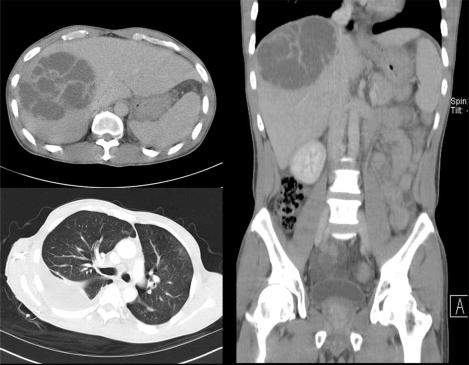

A syndrome of community acquired liver abscess caused by highly virulent hypermucoviscous, rmpA positive Klebsiella pneumoniae strains occurs with high incidence in Asia. We here report a case complicated by metastatic infection, to our knowledge, the first one described in Northern Europe. This and other recently reported cases indicate the emergence of this severe syndrome outside of Asia.